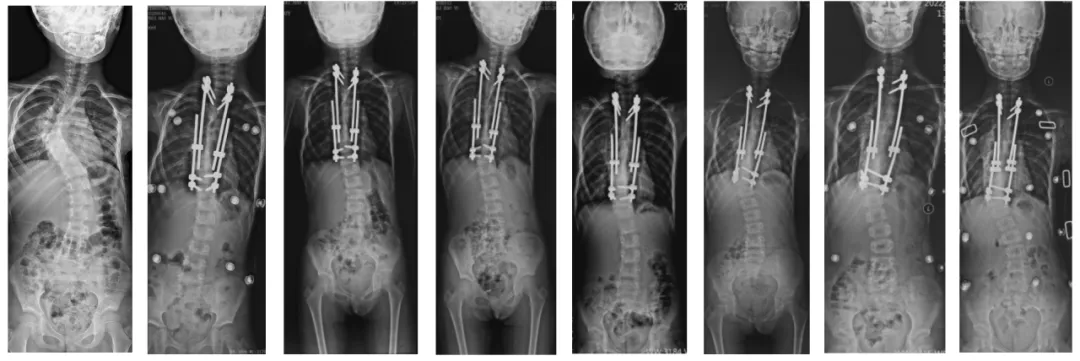

(1) May 10, 2019, growth rod implantation, pre- and post-operative comparisons

(2) 2020-01-15, the first growth rod adjustment: left concave side braced 1.5cm; right convex side braced 1.2cm;

(3) 2020-07-23, the second growth rod adjustment: left concave side stretched 1.5cm; right convex side stretched 1.2cm;

(4) 2021-03-26, the third growth rod adjustment: left concave side propped open 1.5cm; right convex side propped open 1.0cm;

(5) 2021-10-14, the fourth growth rod adjustment: left concave side stretched 1.0cm; right convex side stretched 0.5cm;

(6) 2022-05-22, the fifth growth rod adjustment: bilaterally propped open 1.0cm;

(7) 2023-01-11, both sides were stretched 1.0cm, and one domino on each side was added;

Preoperative → growth rod implantation → full-length piece orthotopic after 6 adjustments